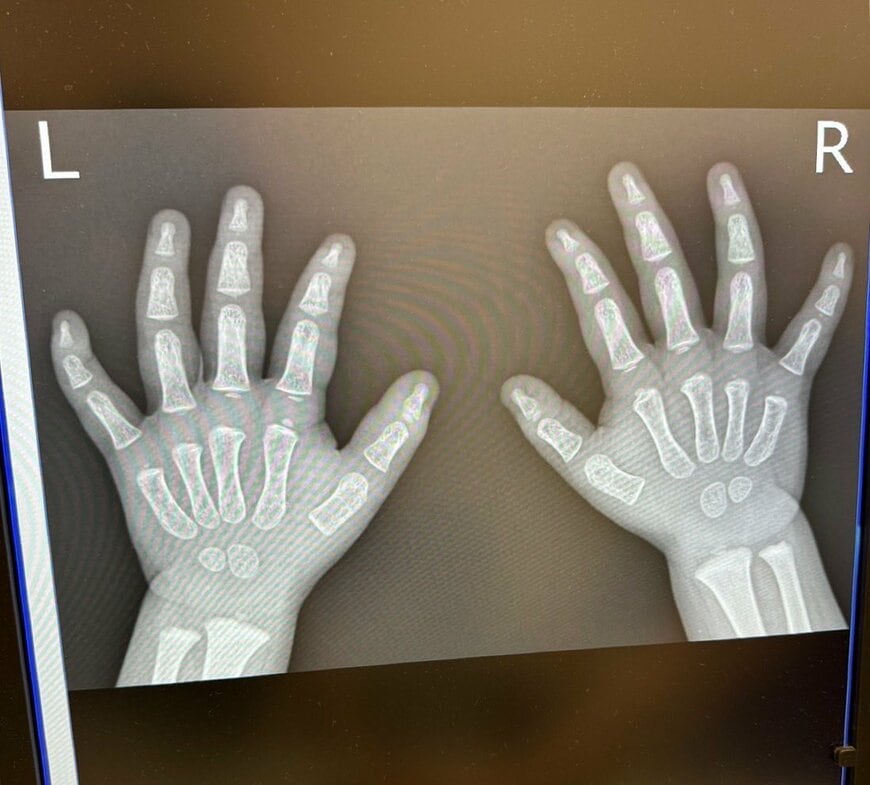

「手を痛めてレントゲン撮ったんだけど可愛いすぎて先生と一緒に笑ったww」そんなコメントとともに投稿されたのは1枚の写真でした。

レントゲンに写っていたのは、一目見てお子さんだと分かる小さな両手。指の骨もひとつひとつが丸みを帯びており、思わず「かわいい!」と言ってしまいそうになりますね。